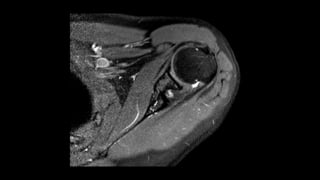

O documento aborda lesões no ombro, dividindo-as por faixas etárias: fraturas de clavícula em crianças, luxações em adultos e fraturas do úmero proximal em idosos. Descreve também técnicas de avaliação radiográfica e suas variações, incluindo incidências específicas para diagnóstico. Além disso, são mencionados métodos de imagem alternativos para a avaliação de partes moles e condições articulares.